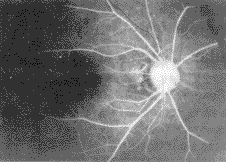

活动病变期FFA过程中渗出性视网膜色素上皮脱离病例,在造影早期色素上皮缺损区可显示 荧光,但在渗出液区呈现荧光遮蔽现象,在造影过程中荧光斑点逐渐向神经上皮脱离区内扩 散加强,至造影晚期仍有荧光积存边缘清晰,成池样外观.在新生血管视网膜下出血病例, 造影过程中动脉期可见花边状、车轮状或绒团状荧光,显示出新生血管形态,见图3,4.

图3 造影动脉期黄斑部显示新生血管形态

图4 造影动脉期黄斑部下方显示新生血管形态